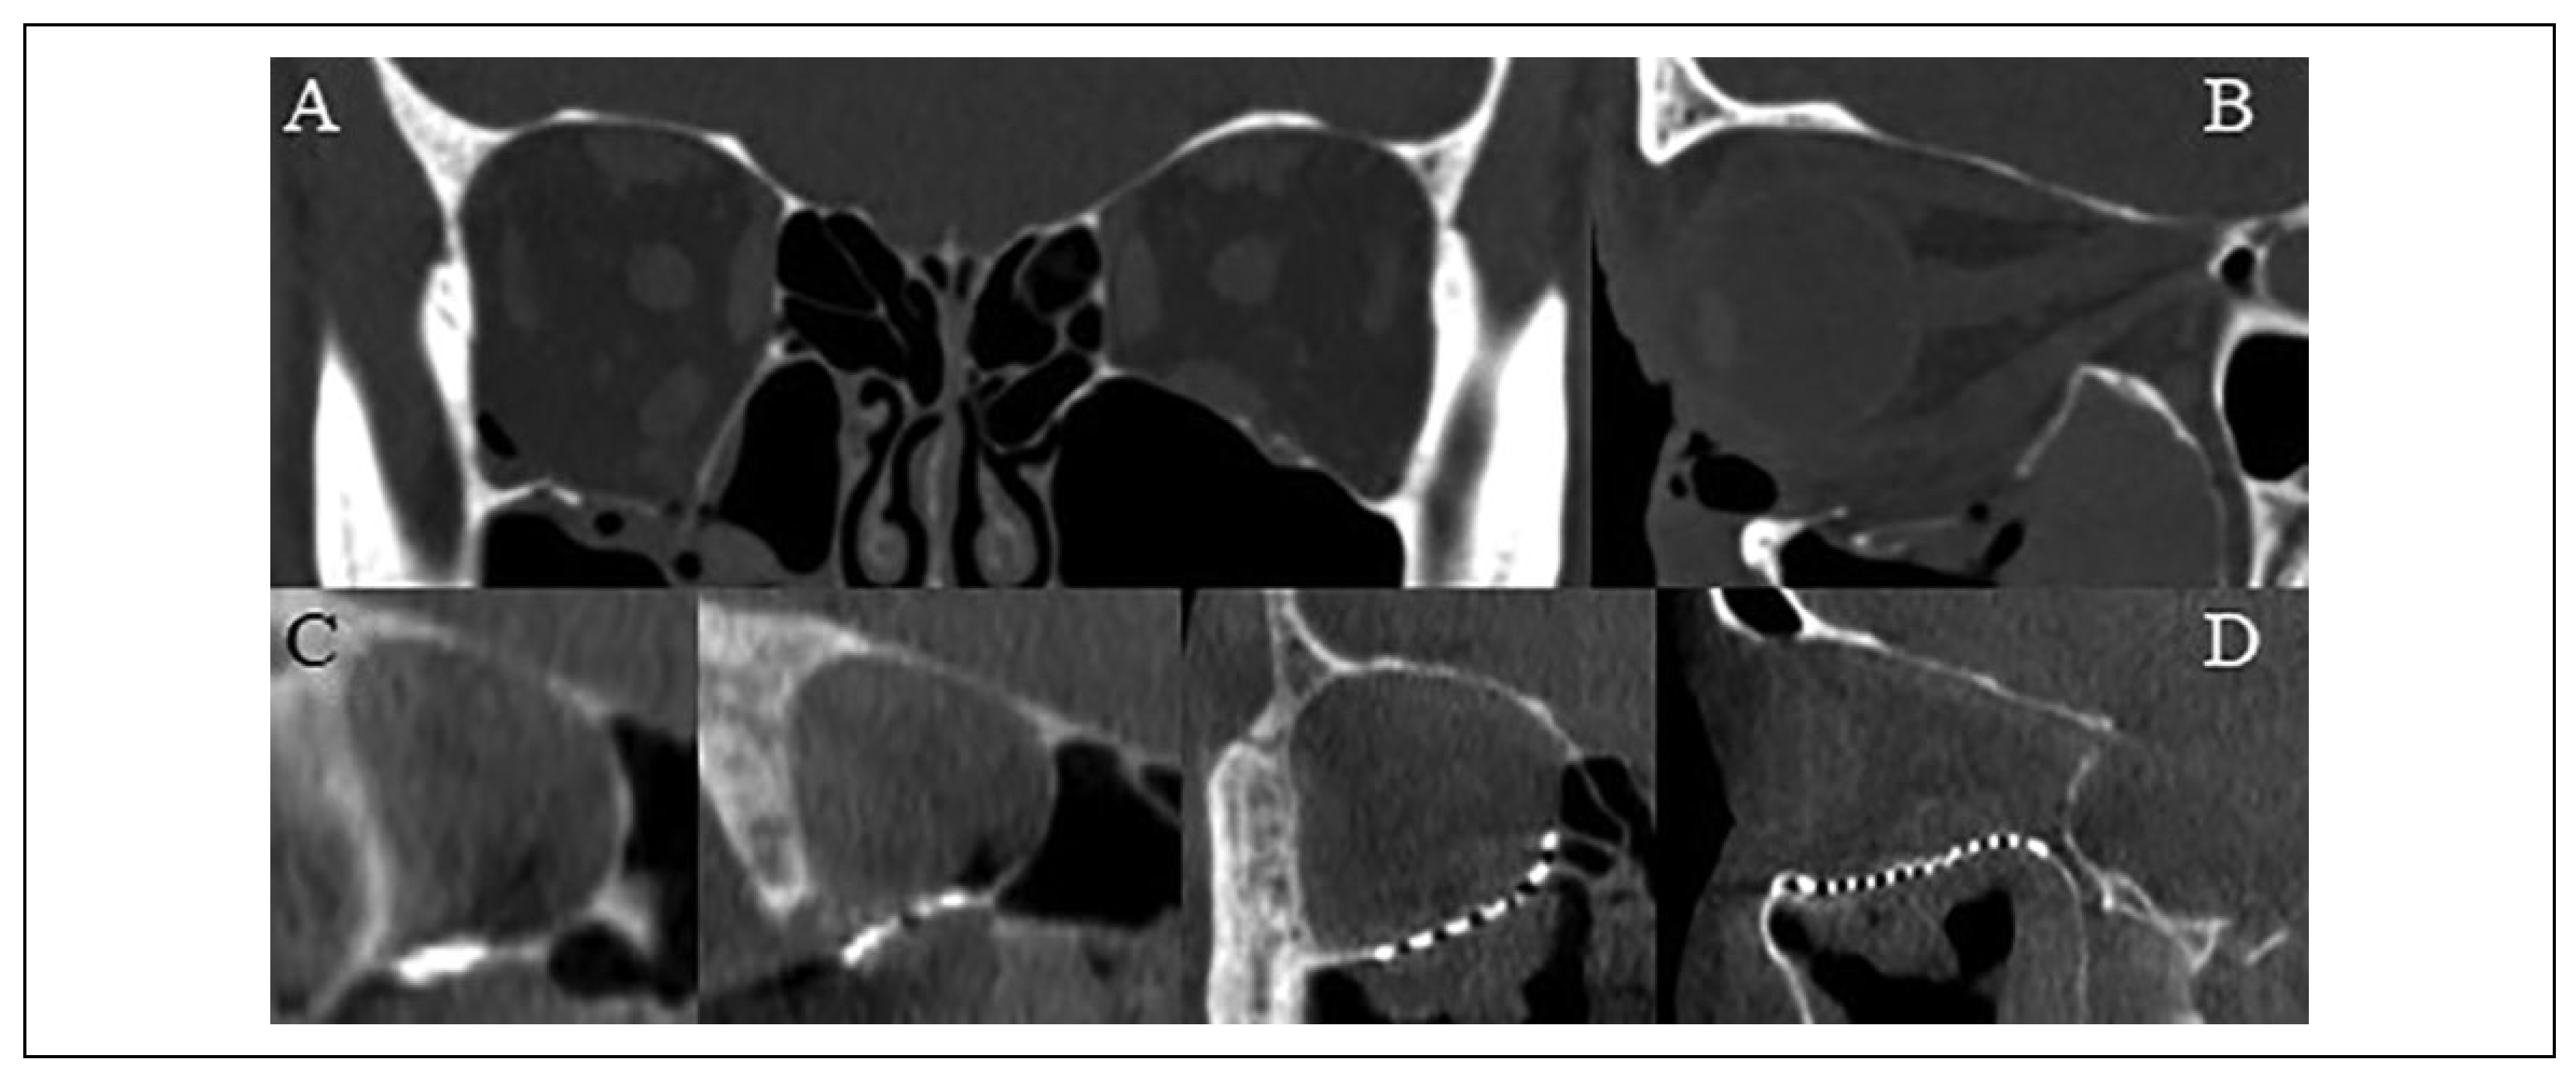

Figure 4.

(A) Coronal and (B) sagittal slices of the pre-operative computed tomography scan demonstrating an isolated right orbital floor blow-out fracture. (C) Coronal and (D) sagittal slices of the intraoperative O-arm “spin” demonstrating favorable position and contour of an “in-house” custom milled titanium mesh plate to reconstruct the orbit.